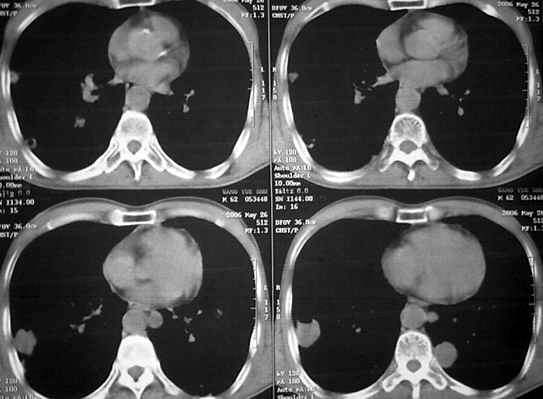

男62肺癌治疗后复查

具体治疗措施不清楚,治疗前空洞很少,请讨论空洞的性质

双肺内及胸壁旁见有多发软组织实性阴影和空洞,实性病变多见有脐凹切迹,贴近胸膜的见有胸膜凹陷征;空洞的壁多为厚薄不均,形态不规则,纵隔内见有较多肿大淋巴结,诊断为双肺内转移性病变。

右肺门软组织块影,右主支气管及中间段支气管管壁明显增厚,两肺内多发结节及大小不等的类圆形薄壁空洞,纵隔内多发肿大的淋巴结;

考虑:1.右中央型肺癌伴两肺广泛性转移及纵隔转移。

2.多发性空洞需和霉菌性空洞鉴别。